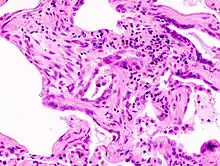

![]() | |

End-stage pulmonary fibrosis of unknown origin, taken from an autopsy | |